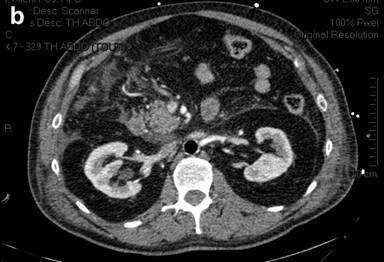

A 58-year-old man with a medical history of dilated cardiomyopathy diagnosed in 2001, with a left ventricular ejection fraction of 35%, was admitted to our ICU in January 2010 following cardiac arrest. In the morning, he had gone hunting, and did not have any symptoms. After returning home, while he was seated and without any prodrome, he presented lost consciousness and fell on the floor. There was no sign of breathing and no cardiac activity. Cardiopulmonary resuscitation was immediately started by his son-in-law, a professional fireman. At minute 20 after cardiac arrest, a professional team of firemen arrived and a semi-automatic cardiac defibrillator delivered 4 electric shocks. At minute 50, an emergency medical team arrived; electrocardiogram revealed asystolia, and intravenous adrenaline (epinephrine) was administered. A return to spontaneous cardiac activity was obtained at minute 80. Cardiopulmonary resuscitation was never interrupted during these 80 minutes, and no mydriasis was noted. An electrocardiogram showed abnormalities of the ST segment with suspicion of posterior myocardial infarct. The patient was transferred to our University Hospital. Coronarography showed no sign of arterial obstruction, and the left ventricular ejection fraction was 50%. An intra-aortic balloon pump was begun. The patient was then admitted to our ICU, with a presumed diagnosis of cardiac arrest secondary to ventricular arrhythmia, complicating dilated cardiomyopathy. The Organ Dysfunction and/or Infection (ODIN) score [4] at admission was 4 and the Simplified Acute Physiology Score (SAPS II) score [5] was 76 on the first day of admission, reflecting the poor prognosis of the patient. Hemodynamic status was initially stable under adrenaline infusion and intra-aortic balloon pump. As there was severe hypoxia with signs of aspiration pneumonia, antibiotic therapy directed against gram-negative and anaerobic bacteria was started. Abdominal volume was increased, with tension, but without diarrhea or digestive bleeding (Figure 1). Biologically, the lipase concentration was 866 IU/L (reference range: 0-60 IU/L). The arterial lactate concentration measured after the prolonged cardiopulmonary resuscitation was 10 mmol/L (reference range: 0.3-2.5 mmol/L); it rapidly decreased to 2.5 mmol/L 24 hours after admission to the ICU. During the ICU stay, the arterial lactate concentration remained normal. The patient was oliguric, with acute renal failure and metabolic acidosis; therefore, continuous veno-venous hemodiafiltration was started. Therapeutic hypothermia using an external cooling device to a target temperature of 33°C was carried out during the first 24 hours. In the following days, the intra-aortic balloon pump and adrenaline were stopped, hypoxia rapidly improved, and renal function normalized. However, abdominal examination did not improve, and there was no sign of awakening despite the cessation of sedation. An abdominal CT scan confirmed the diagnosis of acute pancreatitis with a CT severity index of 4 (Figure 2), and a cerebral CT scan revealed diffuse hypodensity with severe ischemic brain edema. After eight days in the ICU, in the absence of awakening, a therapeutic limitation was decided, leading to death.

Figure 2. Abdominal CT scan showing acute pancreatitis with a CT severity index of four. |